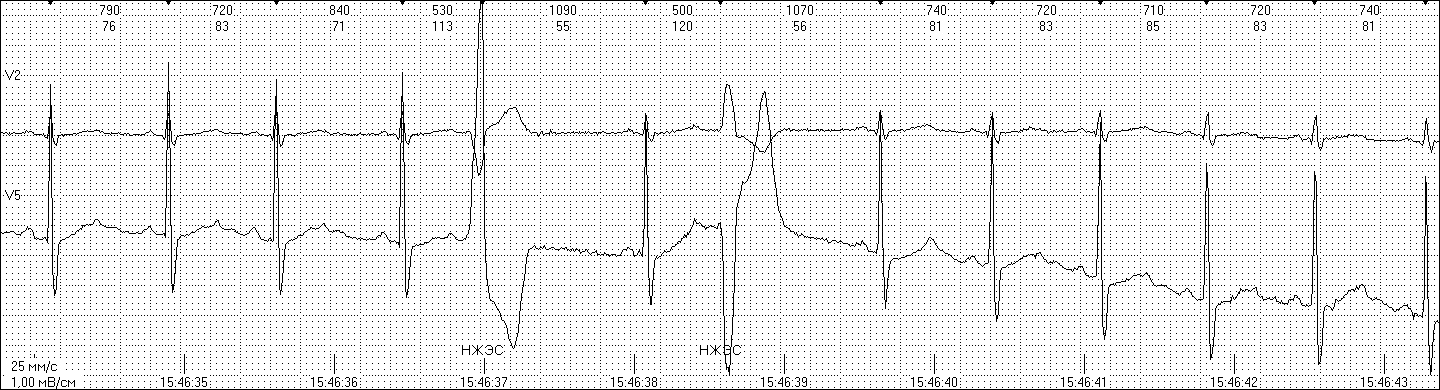

Так же выявлены нарушения внутрижелудочковой проводимости различной степени, суправентрикулярные экстрасистолы (в том числе с аберрацией желудочкового комплекса) (рисунок 5).

Рис. 5. Политопные желудочковые экстрасистолы у испытуемого 50 лет

на высоте 4800 м.